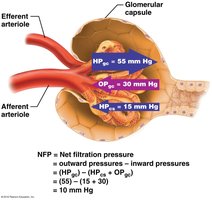

Filtration in the glomerulus is driven by hydrostatic and osmotic pressures. The net filtration pressure (NFP) determines the amount of filtrate produced.

HPgc: Hydrostatic pressure in glomerular capillaries (forces fluid out).

HPcs: Hydrostatic pressure in capsular space (opposes filtration).

OPgc: Osmotic pressure of plasma proteins (draws fluid back in).

Equation:

Typical values:

Note: Filtration stops if HPgc drops by ~15%. Blood pressure must remain high for filtration to continue.